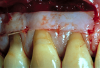

Fig 13. Preoperative retracted view showing extent of recession in a patient with composite restorations that had been placed to cover exposed roots and noncarious cervical lesions.

Figure 13

A female patient presented with composite restorations along the gingival margins that had been placed in an attempt to correct the appearance of gingival recession (Figure 13). The extent of the recession was visible in her smile, and the patient desired improved esthetics.

The composite restorations were removed in anticipation of covering the roots with ADM; this, however, exposed a deficiency in the underlying enamel. The patient and restorative dentist planned the position of a new cementoenamel junction (CEJ) using restorative material. This was accomplished using a glass-ionomer material—which bonds to dentin—on the dentin surfaces covered by a veneer of composite that would polish easily, provide a more esthetic appearance, and bond to the enamel at the coronal aspect of the restoration. This bilayer approach also would prevent marginal leakage around the restorations.

Once the “new” CEJ was established, a tunnel flap was created to enable placement of the ADM through the sulcus. The attachment to the tooth and underlying bone was dissected using a series of precision micro-instruments (eg, Allen Oral Plastic Surgery Kit, Hu-Friedy) designed for oral plastic surgery. The papillae were also loosened from the facial to the palate. This provided ample working room and access with minimal trauma to the patient and minimal postoperative complications or discomfort.26